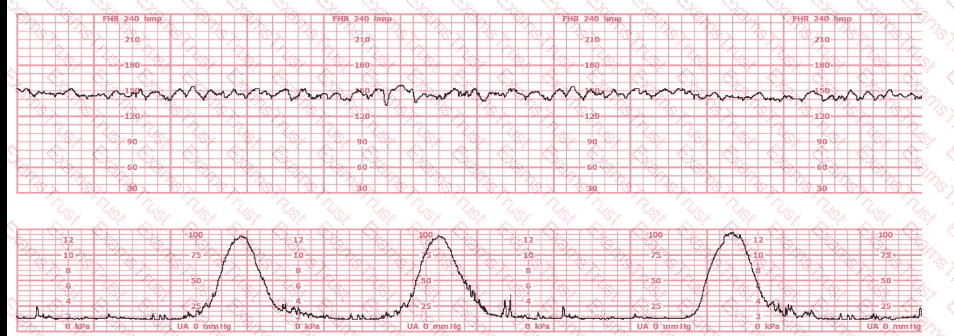

The decelerations seen in the fetal monitoring tracing shown are best described as:

This tracing reflects